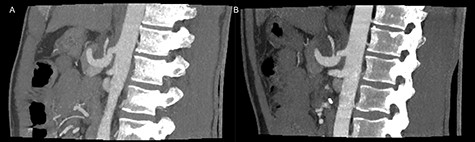

The patient was discharged on the third postoperative day, but readmitted 4 days postoperatively due to a minor abdominal wound dehiscence, which was sutured under general anesthesia. On follow-up computed tomography the arterial stenosis was repealed and the pseudoaneurism collapsed (Fig. 3).

Postoperative inspiratory (A) and expiratory (B) computed tomography scan with repealed hook formation as well as stenosis of the celiac artery.